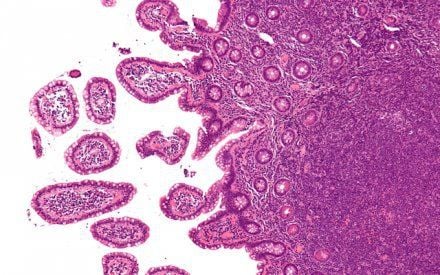

Tại Bệnh viện, bệnh nhân được bác sĩ thăm khám kỹ lưỡng và làm các xét nghiệm cần thiết. Kết quả xét nghiệm máu và tủy đồ cho thấy số lượng tế bào bất thường tăng cao, nghi ngờ bệnh lý ác tính về máu. Tiếp đó, kết quả chụp PET/CT phát hiện nhiều hạch trung thất và hạch mạc treo – dấu hiệu gợi ý tổn thương u lympho. Các bác sĩ tiến hành sinh thiết tổn thương, hội chẩn nhóm chuyên ngành ung thư hệ tạo máu và đưa ra chẩn đoán xác định: U lympho không Hodgkin tế bào B lớn lan tỏa (Diffuse Large B-Cell Lymphoma – DLBCL).

Theo các bác sĩ Khoa Huyết học Lâm sàng, u lympho không Hodgkin tế bào B lớn lan tỏa (DLBCL) là thể bệnh phổ biến nhất trong nhóm u lympho không Hodgkin. Bệnh xuất phát từ tế bào B – một thành phần của hệ miễn dịch, khi bị đột biến sẽ tăng sinh mất kiểm soát và hình thành các khối u ác tính.